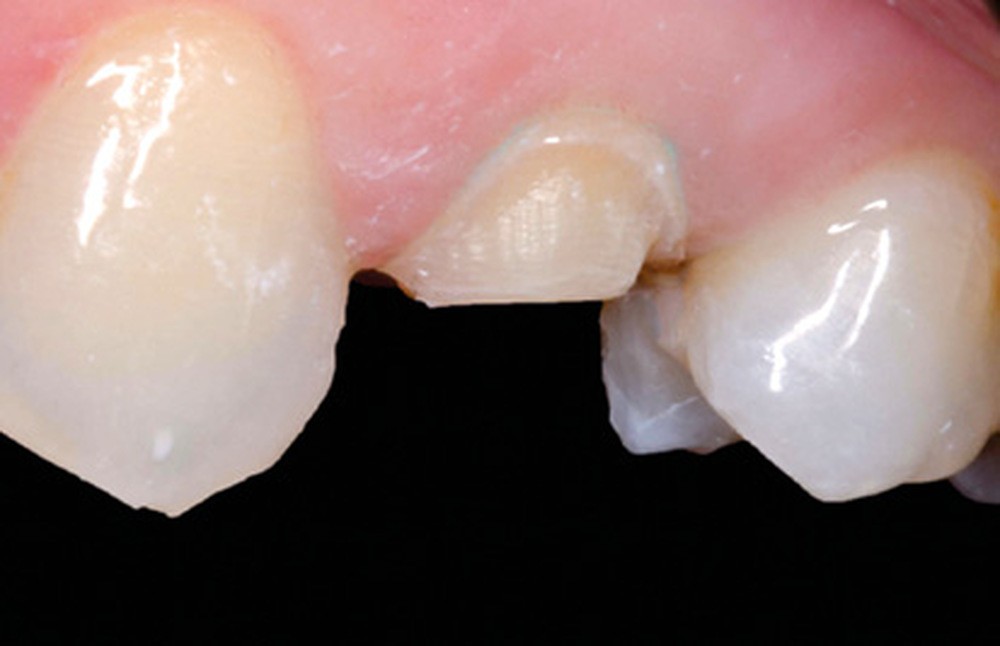

Mme B. se présente au cabinet pour une douleur au niveau de la 24. La dent présente une ancienne restauration avec une lésion carieuse, ainsi qu’une fêlure en mésial avec une pulpite irréversible. La décision est prise de dévitaliser la dent puis de la restaurer par un veneerlay (fig. 11).

Une empreinte optique de l’arcade, de l’antagoniste, ainsi qu’une empreinte de l’occlusion sont réalisées avant la préparation. Tous ces éléments vont aider le prothésiste dans le dessein de sa restauration. Le fichier est ensuite gommé au niveau de la dent préparée, puis enregistré (fig. 12 et 13).

La pièce prothétique est dessinée sur un logiciel de modélisation dentaire, puis elle est imprimée en résine calcinable et transformée en céramique (disilicate de lithium) par technique pressée (fig. 14).